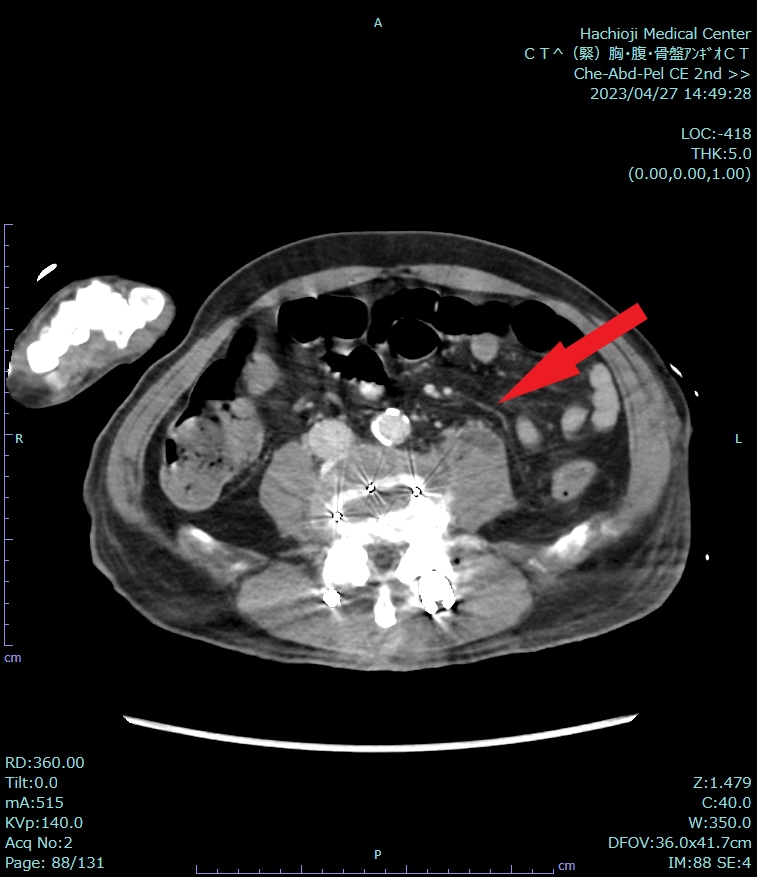

来院時には呼吸困難の他、CRP20mg/dlと炎症反応高値を認めていたため、熱源精査もかねて造影CTを施行した。炎症があれば血流が増加することから、炎症を生じている部位の増強効果がみられるため、異常所見が明瞭化する。特に膿瘍はある程度時間が経つと辺縁がよく造影される低吸収域がみられることが知られている。したがって、炎症反応が高く、腹腔内や骨盤腔内に炎症性疾患が疑われる場合は、造影CTによる熱源の検索が望まれる。本症例では、単純CTでは感染源の同定は困難であったが、造影することによって、右大腰筋に膿瘍があることがわかった。本症例のように、入院直後であり、情報が少ない場合はある程度すべての疾患も網羅できるように撮像する必要がある。ただし、単純CTに加え、造影CTでは動脈相と実質相の撮像を必要となり、被ばく量が増加するため、本当にその撮像が必要かはよく考えなければならない。

CT技術や撮像プロトコル設定について